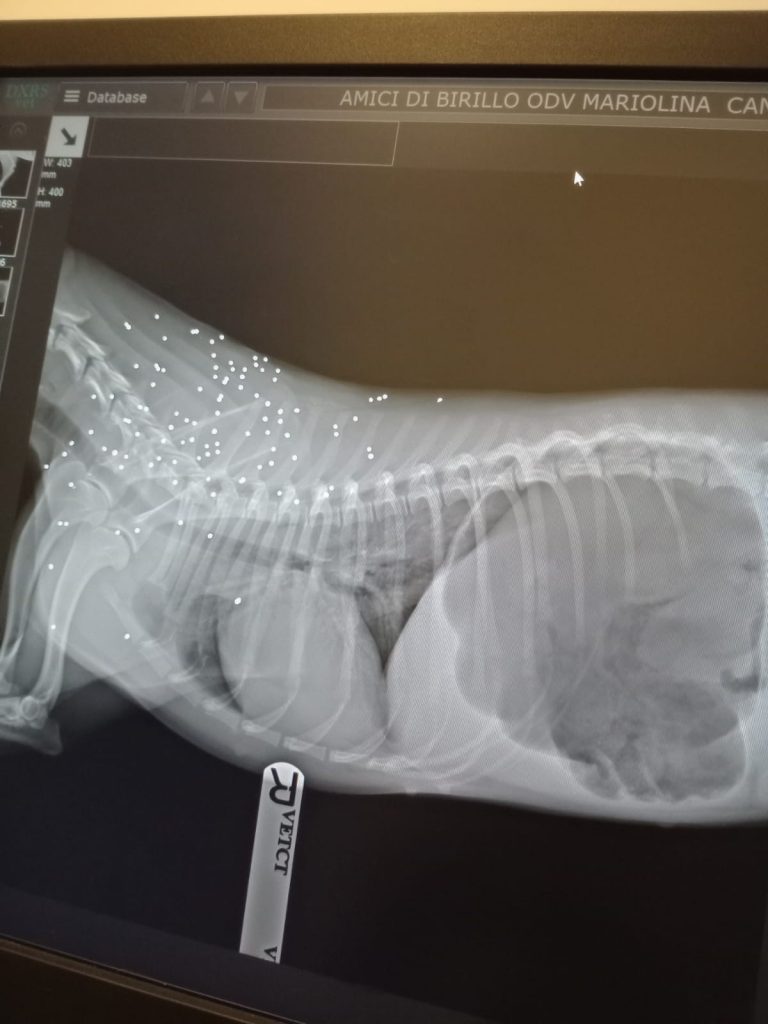

Quei puntini bianchi che vedete nella prima foto sono pallini di un fucile...le hanno sparato e probabilmente per fuggire o è stata investita o si è fatta male in altra maniera lussandosi e frattura la rotula.